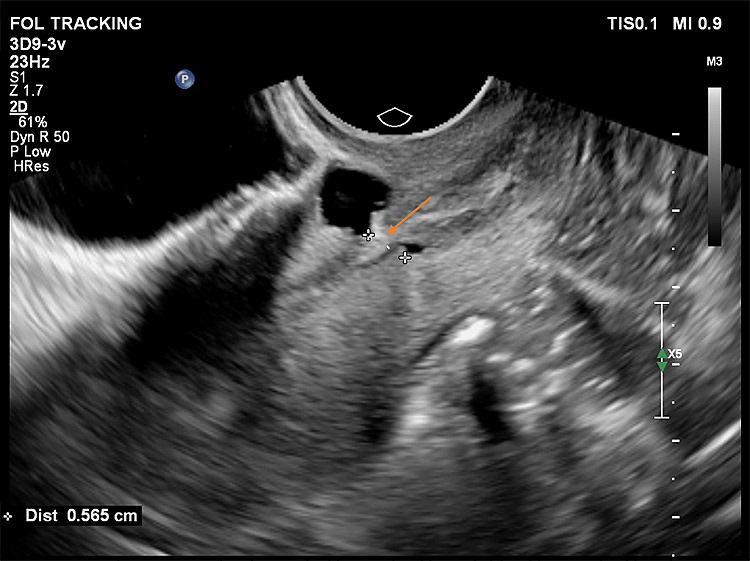

Στις παρακάτω εικόνες από ενδοκολπικό υπέρηχο φαίνονται παραδείγματα επιπέδου τρία προηγμένης τεχνολογίας υπερηχογραφικής μελέτης όπου σημαντικές λεπτομέρειες σε ό,τι αφορά τη θέση, το μέγεθος και την ανατομική συσχέτιση της Ισθμοκήλης, είναι εμφανή με καθαρό τρόπο, επιτρέποντας την εκτίμηση κατά πόσο μπορεί να γίνει χειρουργική επέμβαση ή όχι, και αν ναι με ποια τεχνική. Όλες οι εικόνες έχουν παραχθεί με υπερηχογραφική μηχανή Philips Elite, Costas Panayotidis operator.

Εικόνα 3: εδώ φαίνεται καθαρά η ένωση της εσωτερικής ενδομητρικής κοιλότητας με την Ισθμοκήλη, στο κέντρο η οποία τροφοδοτεί το γέμισμα της κύστης με υγρό και με αίμα από την ενδομητρικη κοιλότητα, το σημείο ένωσης φαίνεται με το βέλος

Εικόνα 4: δείχνει προεγχειρητική μέτρηση του υπολειπόμενου μυομητρίου για την πιθανή υστεροσκοπική διόρθωση της ισθμοκήλη, το πάχος από μέσα απ’ το ενδομητριακό τμήμα είναι μόλις 5.6 mm όπως φαίνεται με το βέλος